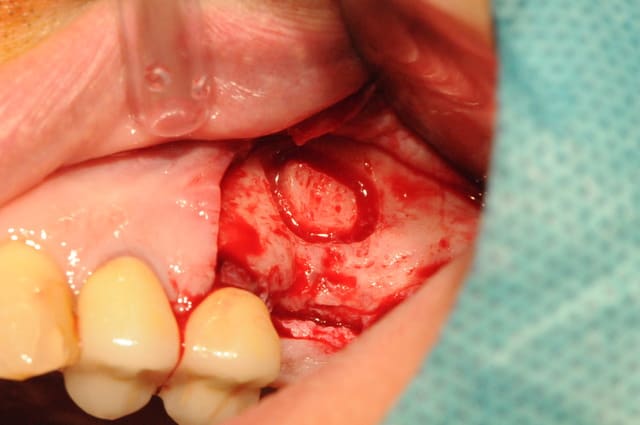

Beau travail dentiste 57. Je ne compte pas commenter l'indication du sinus-lift mais plutot la chirurgie en elle même.

J'ai cependant quelques remarques et certainement quelques conseils pour tes prochains sinus-lift :

- position de la fenêtre latérale : il est pratique de mesurer sur l'OPG ou le scanner la hauteur de crête et de reporter cette mesure in situ, cela t'éviteras de taper dans la corticale et d'avoir un accès décalé et plus génant. Dans le cas où la hauteur de crête est très fine 2-3 mm, il est dans tous les cas fortement conseillé de rester à un minimum de 5mm de cette dite crête et ce afin d'éviter un effondrement crestal difficile à régénerer.

- taille de la fenêtre latérale : elle est dans ton cas acceptable même si j'ai l'habitude d'ouvrir un peu plus ... accès et élévation en sont facilités.

- volet osseux : de par ta préparation à la fraise boule il t'était impossible de repositionner le volet osseux en fin de chirugie. La logique voudrait que tu repousses ce volet dans le sinus afin de créer un "pseudo plafond sinusien". A la vue de tes photos il semblerait que tu es tout de même enlevé ce volet. Est ce que je me trompe ? si oui oublies ma question, si non pourquoi ?